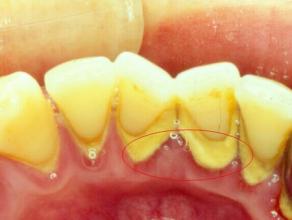

预防牙结石的方法有哪些?由于食物残渣长期在牙齿表面堆积,不及时清理,就容易形成牙结石,影响口腔健康。沈阳康贝佳口腔医生介绍:牙结石是可以预防的,那么预防牙结石有什么方法?下面就让沈阳康贝佳口腔医生为您详细介绍。

1、人们要想有效的预防牙结石的发生,这时就需要人们保障在早、晚刷牙。并且还要在饭后漱口,同时对于有需要的使人们来说,还可以采用牙线的方法进行洁牙。

2、如果预防牙结石失败,这时同样也是能使用洗牙的治疗办法来进行治疗。并且人们在进行洗牙的方法还能对口腔内的牙结石达到治疗粉碎的效果,同时,在治疗时不会对人们又的副作用情况发生。

沈阳康贝佳口腔在洁牙方面所使用的是高频声呐洁牙仪,该技术能进行治疗解决牙结石的发生,同时洁牙还可以修复口腔内的牙周病情况,让患者的牙齿更健康。